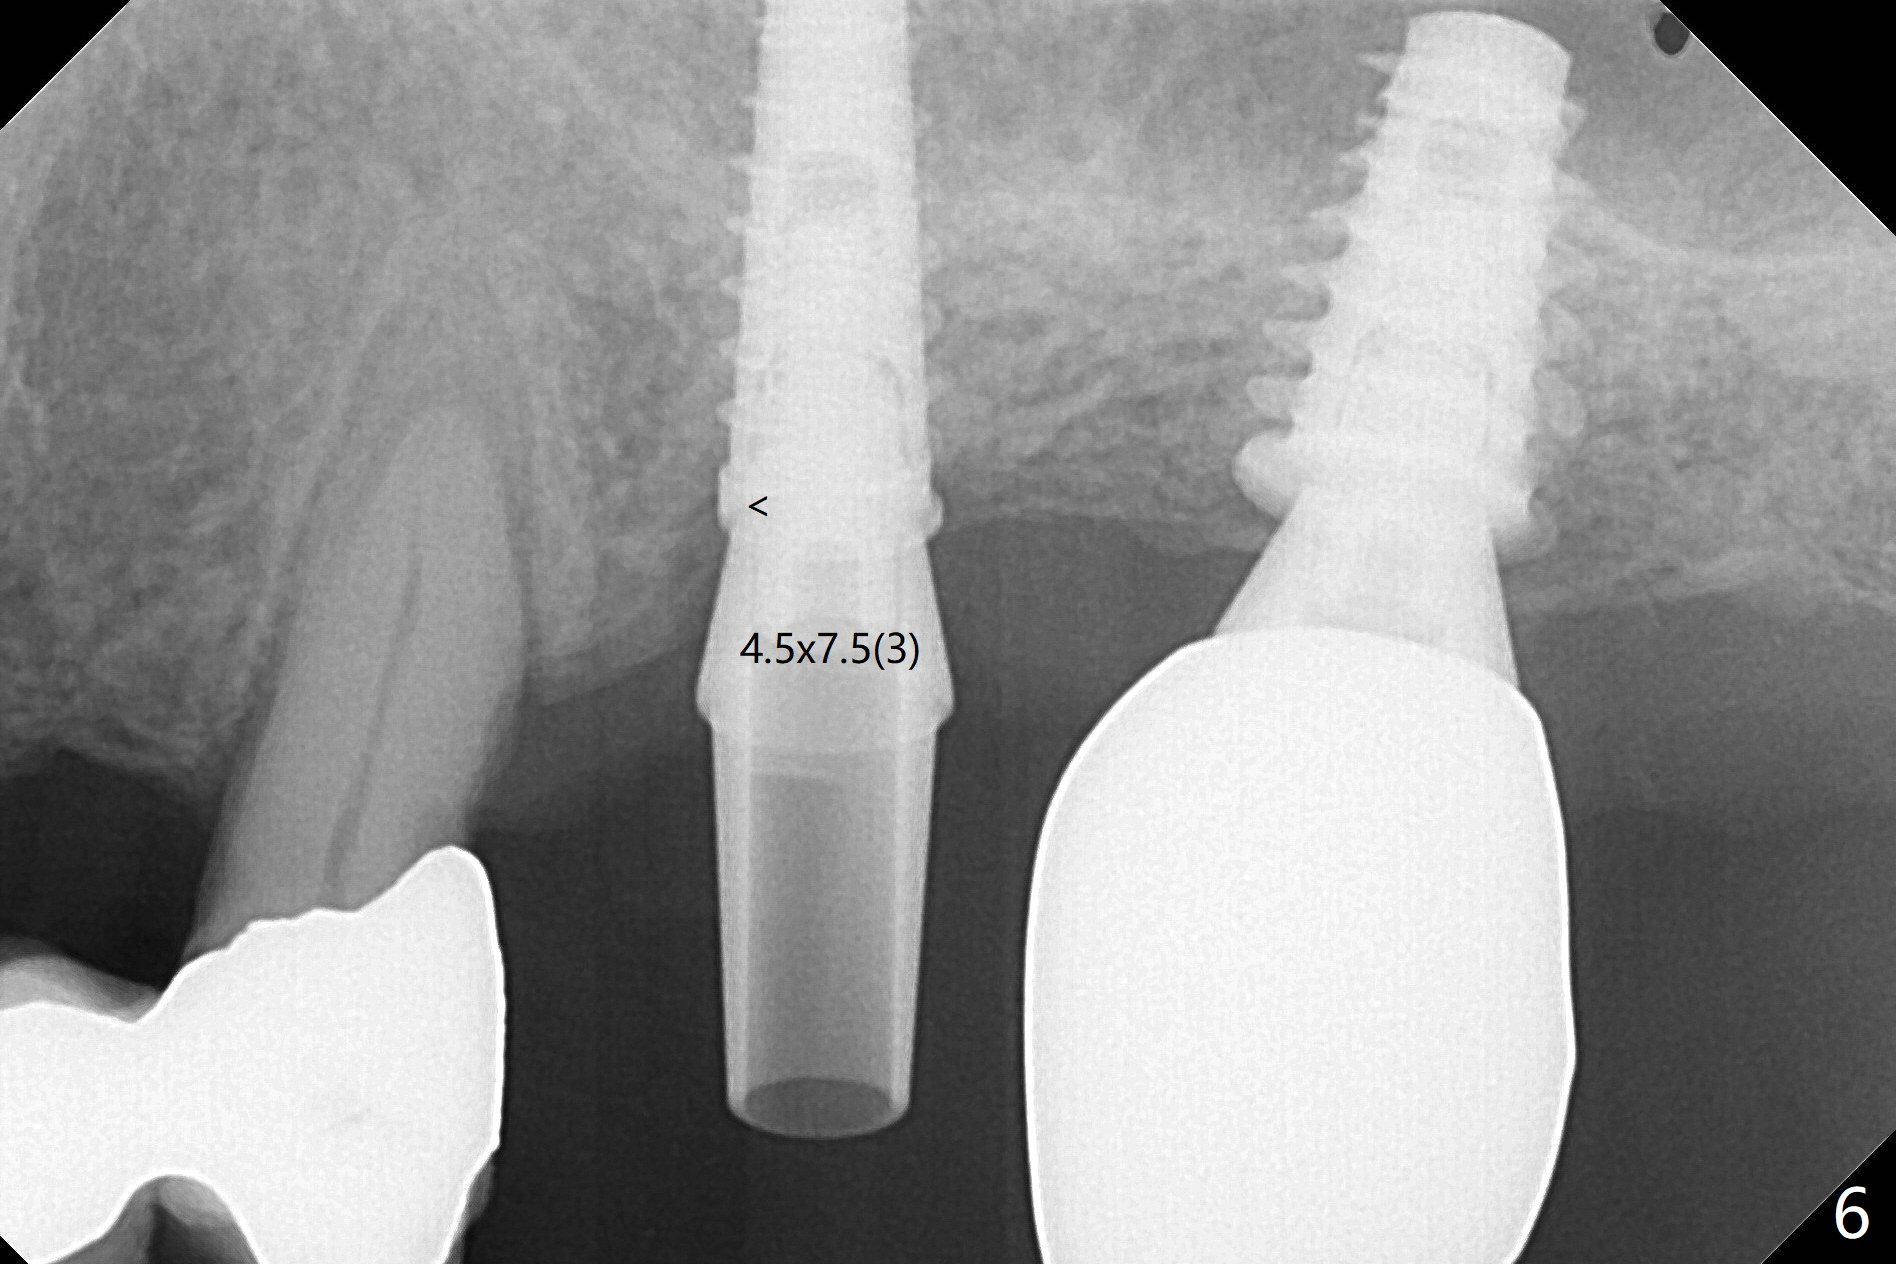

Due to irregular shape of freshly extracted socket at #15, control of depth is difficult. The sinus membrane is perforated after use of bone spreader, probably associated with drills longer than expected. SM taps (5.0 and 5.3 mm) do not achieve stability. When a 5.5x9 mm IBS dummy implant is inserted, initial stability is obtained (Fig.1). Osteotomy at the edentulous area of #14 is uneventful with insertion of a 4x11 mm dummy implant (without involving the sinus floor apparently clinically as well, Fig.1). After adjustment of trajectory, a 4x11 mm definitive implant is placed at #14 with ~ 35 Ncm, while a 6x9 mm implant is placed at #15 with ~35 Ncm (Fig.2 (*: Vanilla Graft with Osteogen)). Periodontal dressing is applied around the abutments and neighboring teeth. There is mild oral and nasal hemorrhage postop. In fact the patient has history of stroke with oral Plavix intake. The medicine stops 4 days preop and is advised to resume after hemostasis is achieved. The patient returns 3 months postop (Fig.3). After changing abutments to 5.5x5.7(3) mm, impression is taken. The crown/abutment at #14 is loose 1 year 10 months post cementation. After use of 5.5 mm profile drill, the crown/abutment is reseated, but the seating is incomplete (Fig.4 <) because of contact of the abutment with the mesial crest (*). A larger profile drill does not help (Fig.5). When a narrower abutment (4.5x7.5(3) mm) is torqued, it appears to be completely seated (Fig.6). After distal surface adjustment of the abutment, impression is re-taken. There are 3 other unfavorable conditions: poor crown/implant ratio and trajectory and #18 missing. The abutment at #14 must have been prepared for parallelism before impression. Return to Upper Molar Immediate Implant, Prevent Molar Periimplantitis (Protocols, Table), Armaments No Deviation Prevent Screw Loosening Xin Wei, DDS, PhD, MS 1st edition 11/28/2017, last revision 02/23/2021